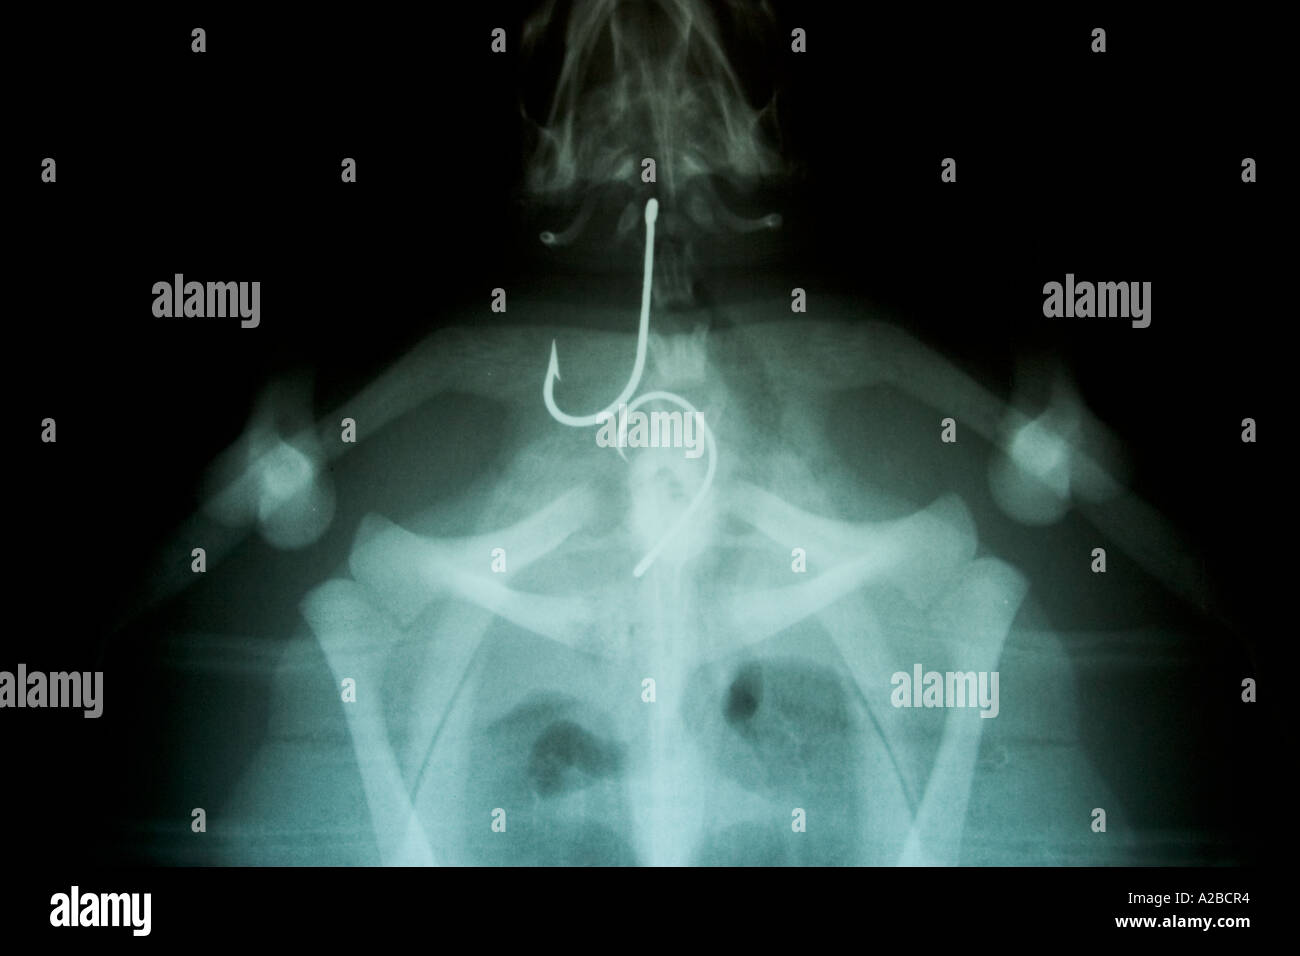

Fish Hook X Ray . Four primary techniques have been described for the removal of fishhooks: The fish hook was advanced, tip and barb cut after. subspecialty consultation should be obtained for fish hooks lodged in the eye, eyelid, or in vital structures (eg,. fishhooks caught in the skin are problematic because of the barbs that are intended to keep fish on the hook. a deep fishhook is one that has penetrated to or past the curve of the hook—the barbed point is directed parallel to or even toward. glick y, fish hook in finger. plain radiograph findings demonstrating a fish hook foreign body in the hand. principles of removal. most embedded fish hooks can be removed in the emergency department. what shape is it (treble hook, single hook)? The physical examination requires a thorough neurovascular exam and,. The choice of removal technique depends.